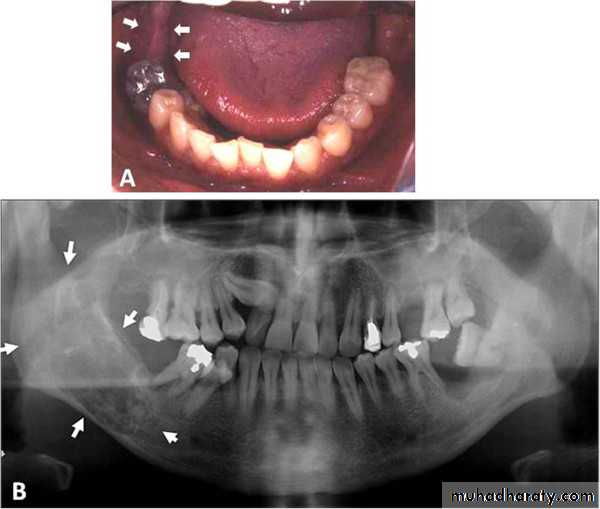

Clinical features: Slow – growing usually central jaw lesion. Painless- unless infected. Expands bone (expansion of buccal and lingual plates) - locally infiltrative and erodes cancellous bone.

Tooth mobility / derangement.Thinning of cortical plates Depressible bone egg -shell cracking sound.

Multilocular radioluscency honey comb or soap bubble appearance.-In unicystic ameloblastoma unilocular radioluscency.

Thinning and expansion of cortical plate. Thinning of lamina dura.

Truncation /Amputation of roots

Ameloblastoma